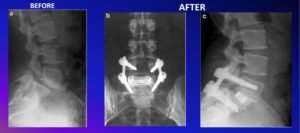

Imaging

- Plain X-rays in the standing position with oblique side view

- CT– best for bony pathology; localize lesion; confirm diagnosis; plan surgery

Surgical Options

- Posterior Fusion with interbody Fusion (TLIF/PLIF)